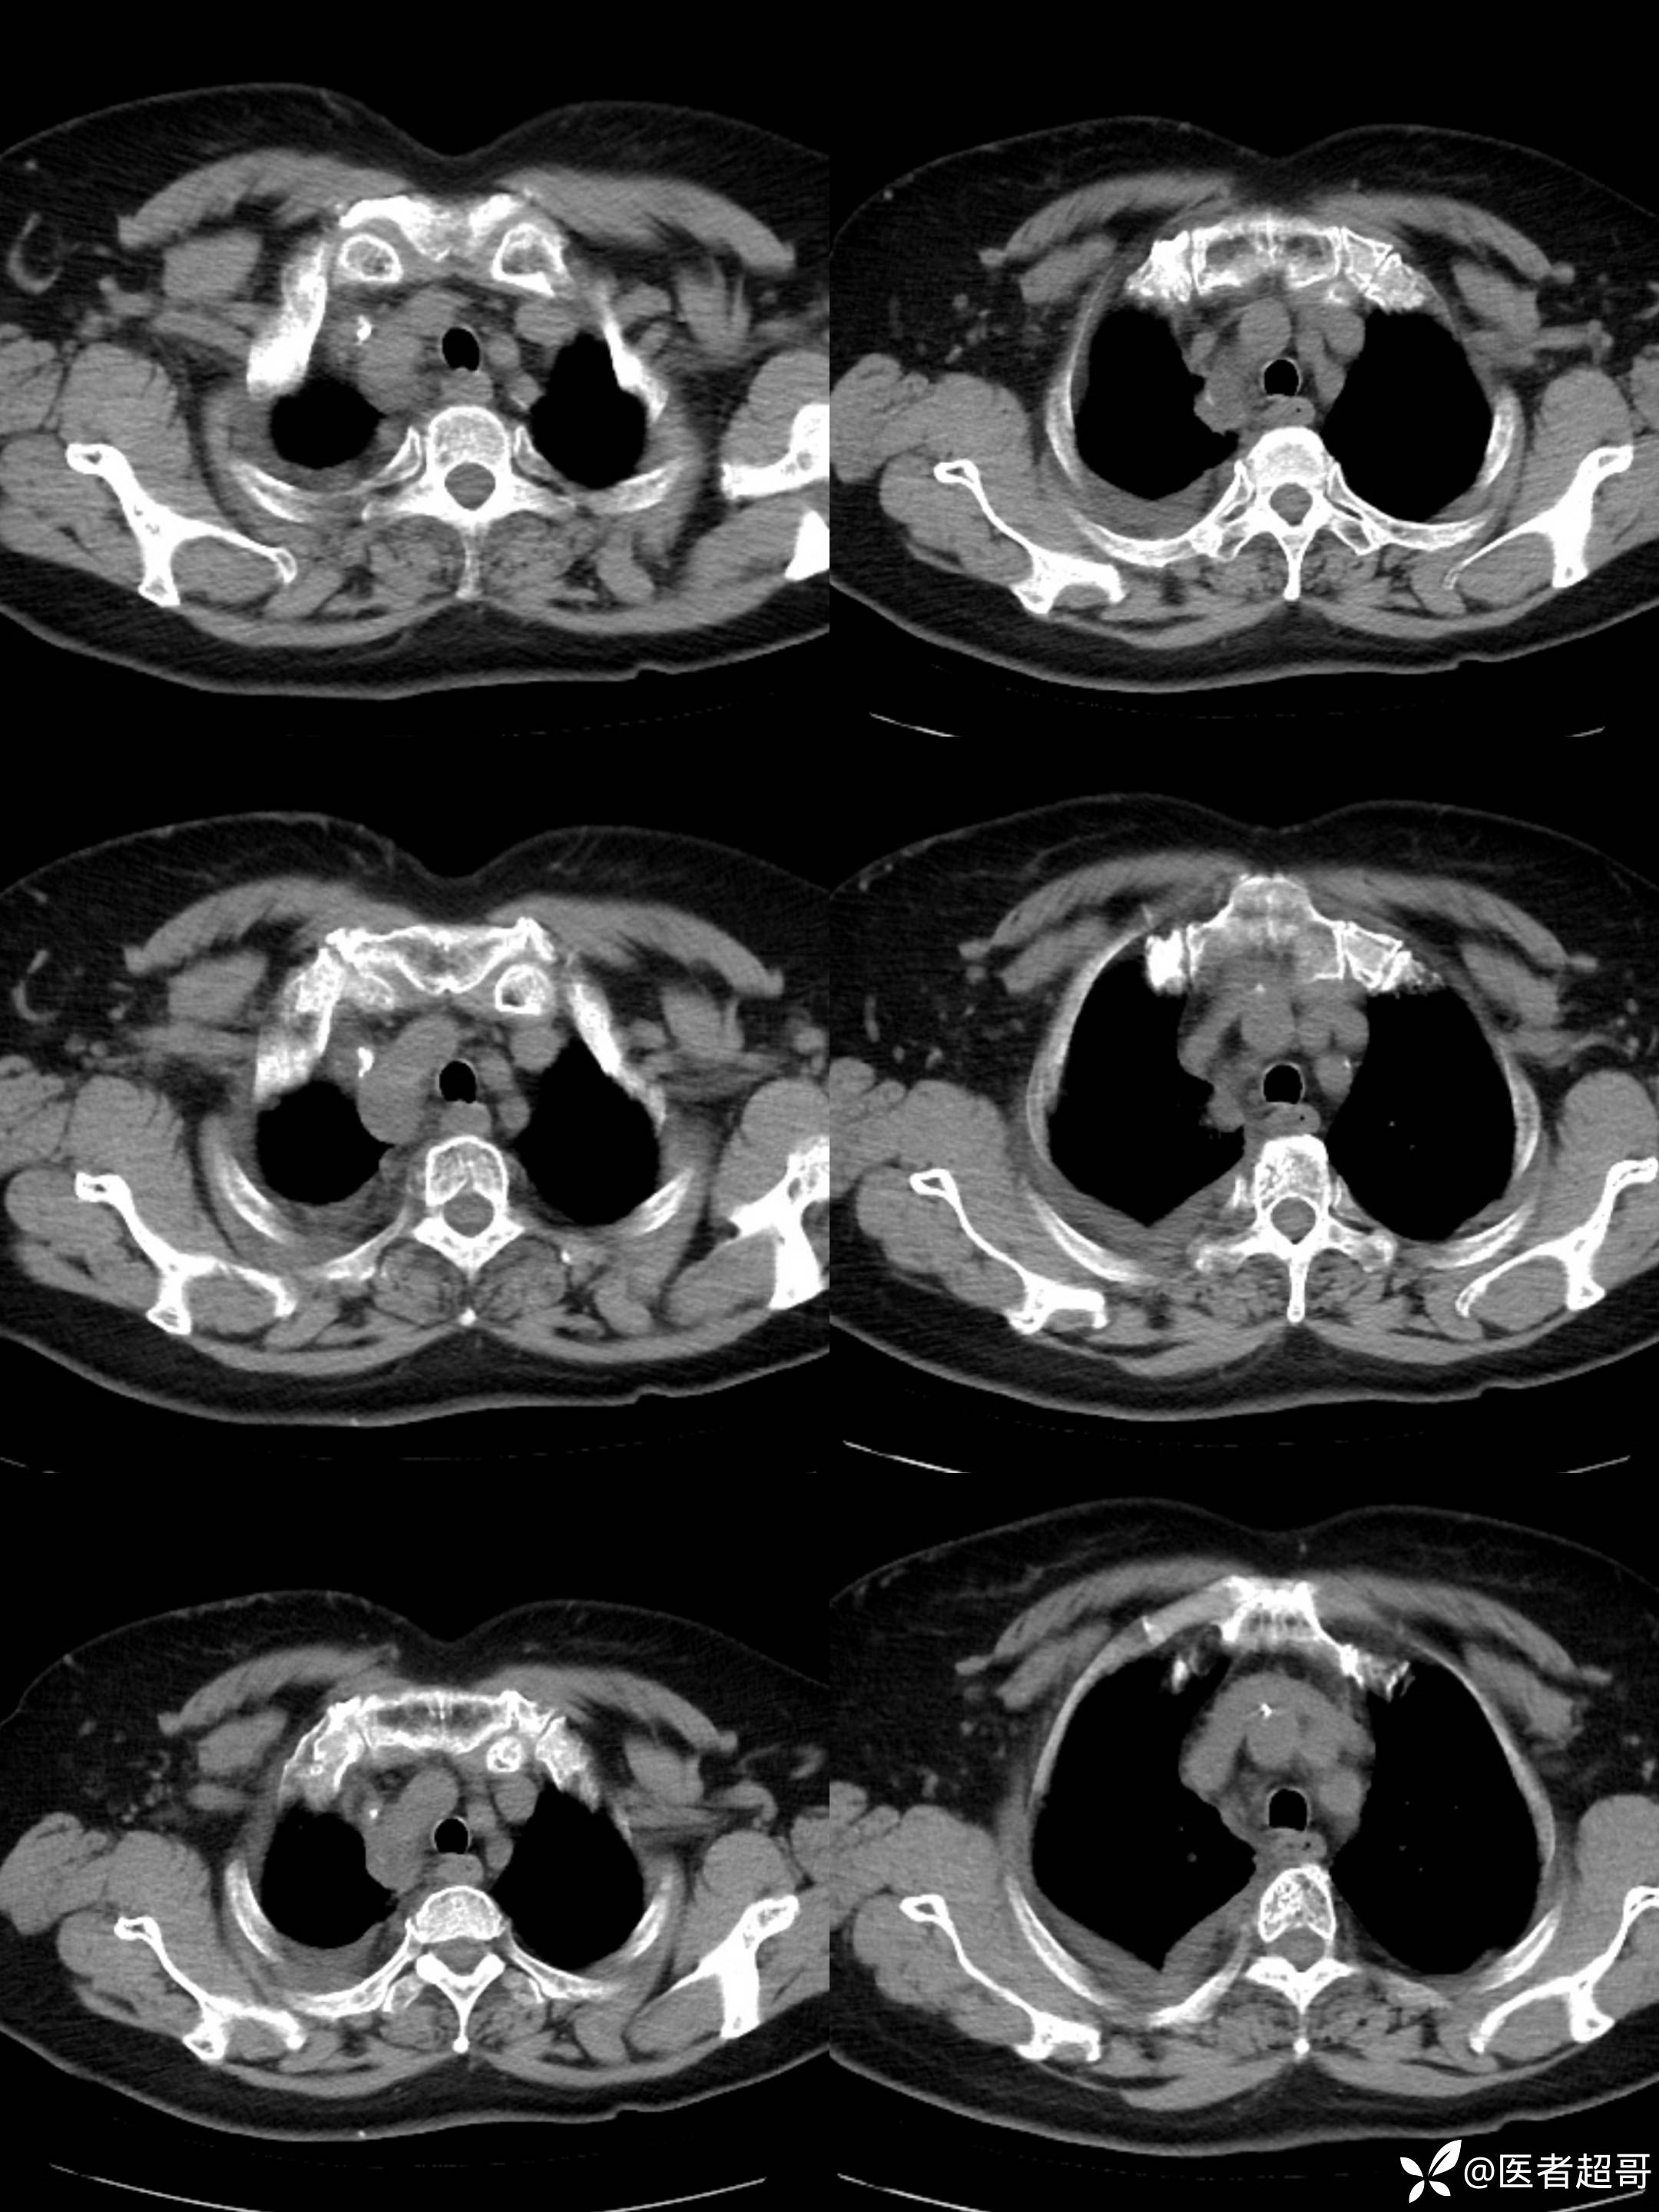

女65岁,患者于一月前无明显诱因突发右胸背部疼痛不适,呈阵发性疼痛

结核特异性细胞(TB-I) 阴性;超敏反应C蛋白(hsCR) 18mg/L ↑,其余血常规正常;

纵隔良性畸胎瘤 (1)